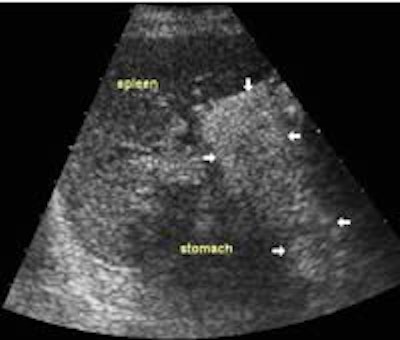

This advantage should be utilized, and to do so the sonographer must be familiar with pancreatic anatomy at different scanning angles. When scanning for lesions it is mandatory to use the longitudinal plane as well as the transverse plane on the pancreatic head and body. The pancreatic tail is not as easily accessible in many planes, but one can often get a good view through the spleen in the scan plane along the intercostal spaces, which often happens to align the transducer with the long aspect of the tail.

- The pancreatic tail is notoriously difficult to spot via the spleen, but with experience the texture of the pancreas becomes more evident, and very good views of the tail can be obtained in more than half of the patients. This view is particularly important for the evaluation of pseudocysts, which are quite common in the tail.

Splenic view:

![]() Image11 |